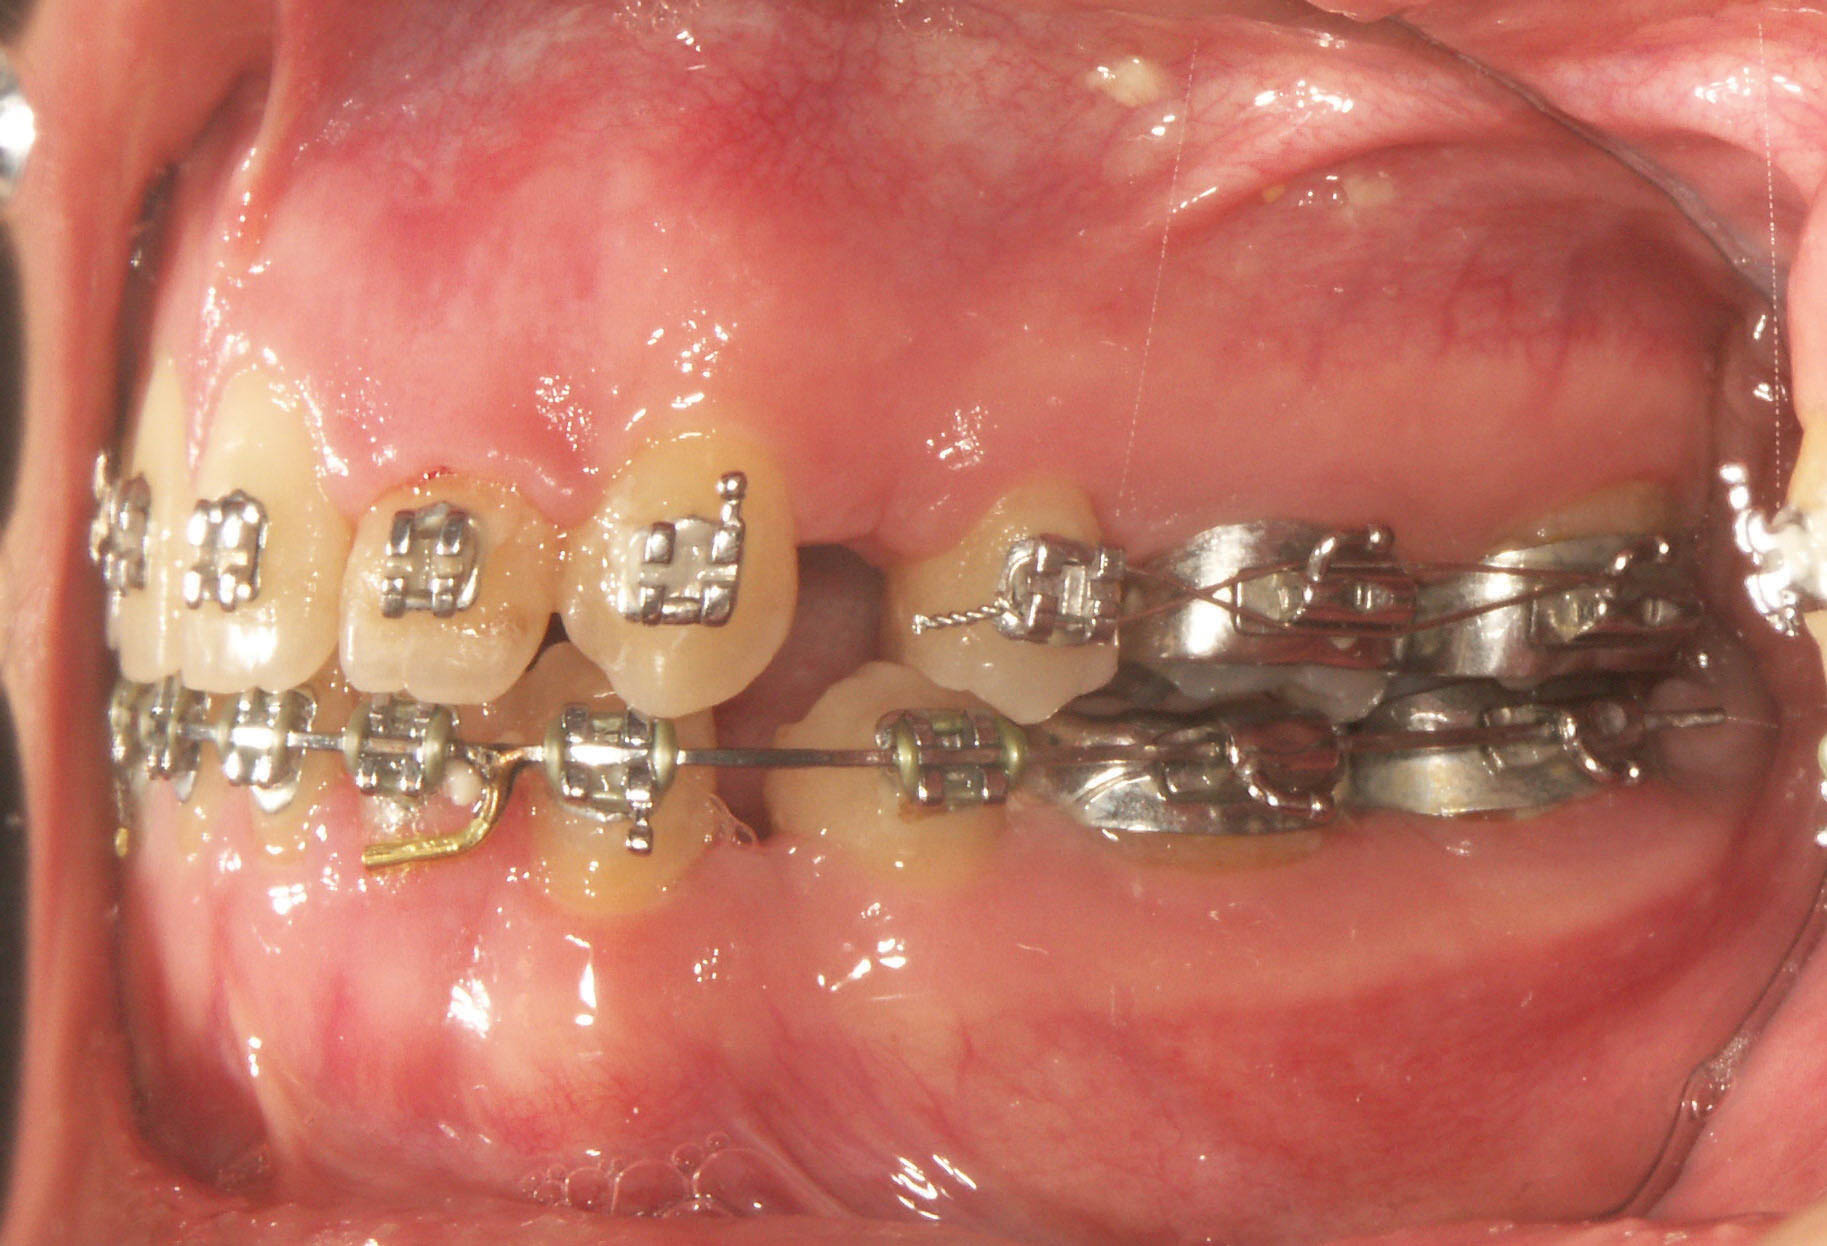

در بستن فضا معمولی (بدون مینی اسکرو) سه حالت داریم (شکل 27-3):

• قدامیها عقب میروند.

• خلفیها جلو میآیند.

• ترکیبی از این دو نوع حرکت.

عقب رفتن قدامیها یا جلو آمدن خلفیها باعث بسته شدن بایت میگردد.